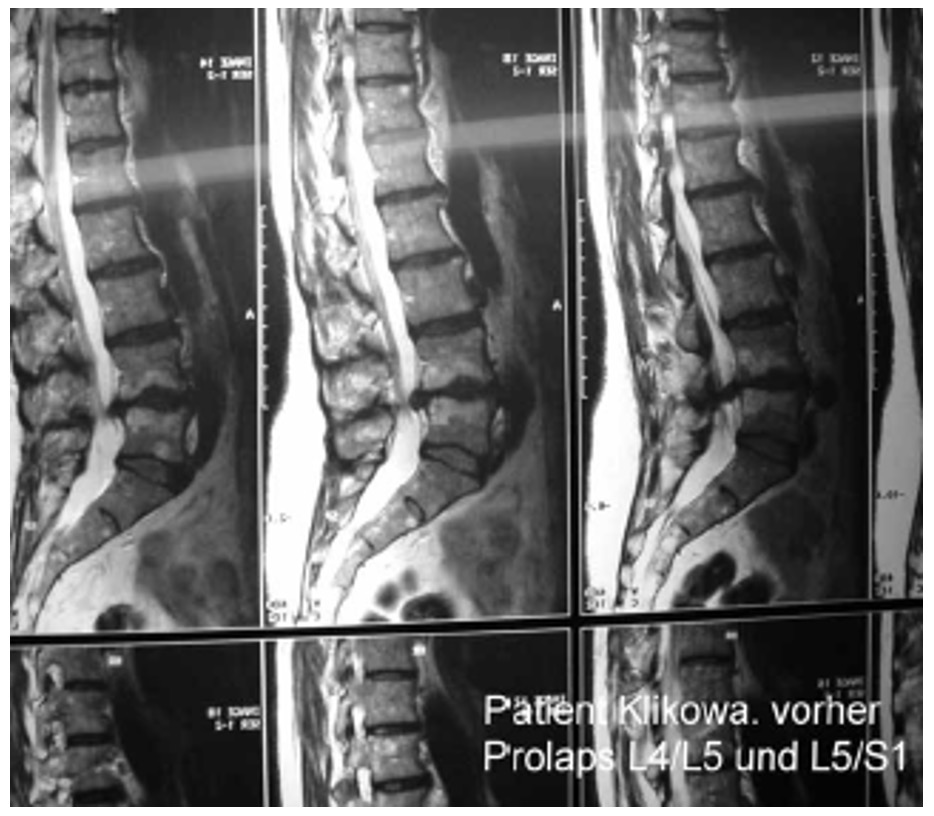

Эффективность лечения оценивалась по данным клинического наблюдения, показаниям электрофизиологических исследований: рентгенографии (включая рентгенографическую компьютерную томографию и магнитно-резонансную томографию (рис. 21а, 21б, 22а, 22б)), параметрам функции внешнего дыхания, показателям гемодинамики при реоэнцефалографии и лазерной допплерографии, компьютерно-оптической топографии позвоночника, электроэнцефалографии, результатам измерения величины электрокожного сопротивления в репрезентативных точках акупунктуры, стабилометрии и др. У всех пациентов независимо от основной патологии при мануальном обследовании выявлены функциональные блокады ПДС, напряжение различных групп мышц (прежде всего в мышцах верхнего плечевого пояса) и наличие в них болевых точек. Выраженность болевого синдрома оценивали по визуально-аналоговой шкале (ВАШ), выраженность тревожной и депрессивной симптоматики определяли по шкале А. Бека.

Рис. 21. Компьютерная томограмма поясничного отдела позвоночника при болевом синдроме

а) ДО проведения Детензор-терапии (отмечается заднецентральная грыжа межпозвонкового диска L4-L5 с компрессией дурального мешка и пролапс межпозвонкового диска на уровне L5-S1)

б) ПОСЛЕ проведения Детензор-терапии (отмечается регресс грыжи и пролапса межпозвонковых дисков)